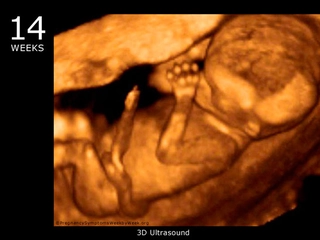

• 14. Hafta: Fetüsün cinsiyeti belirlenebilir. Anne adayı, karnındaki büyümeyi hissedebilir.